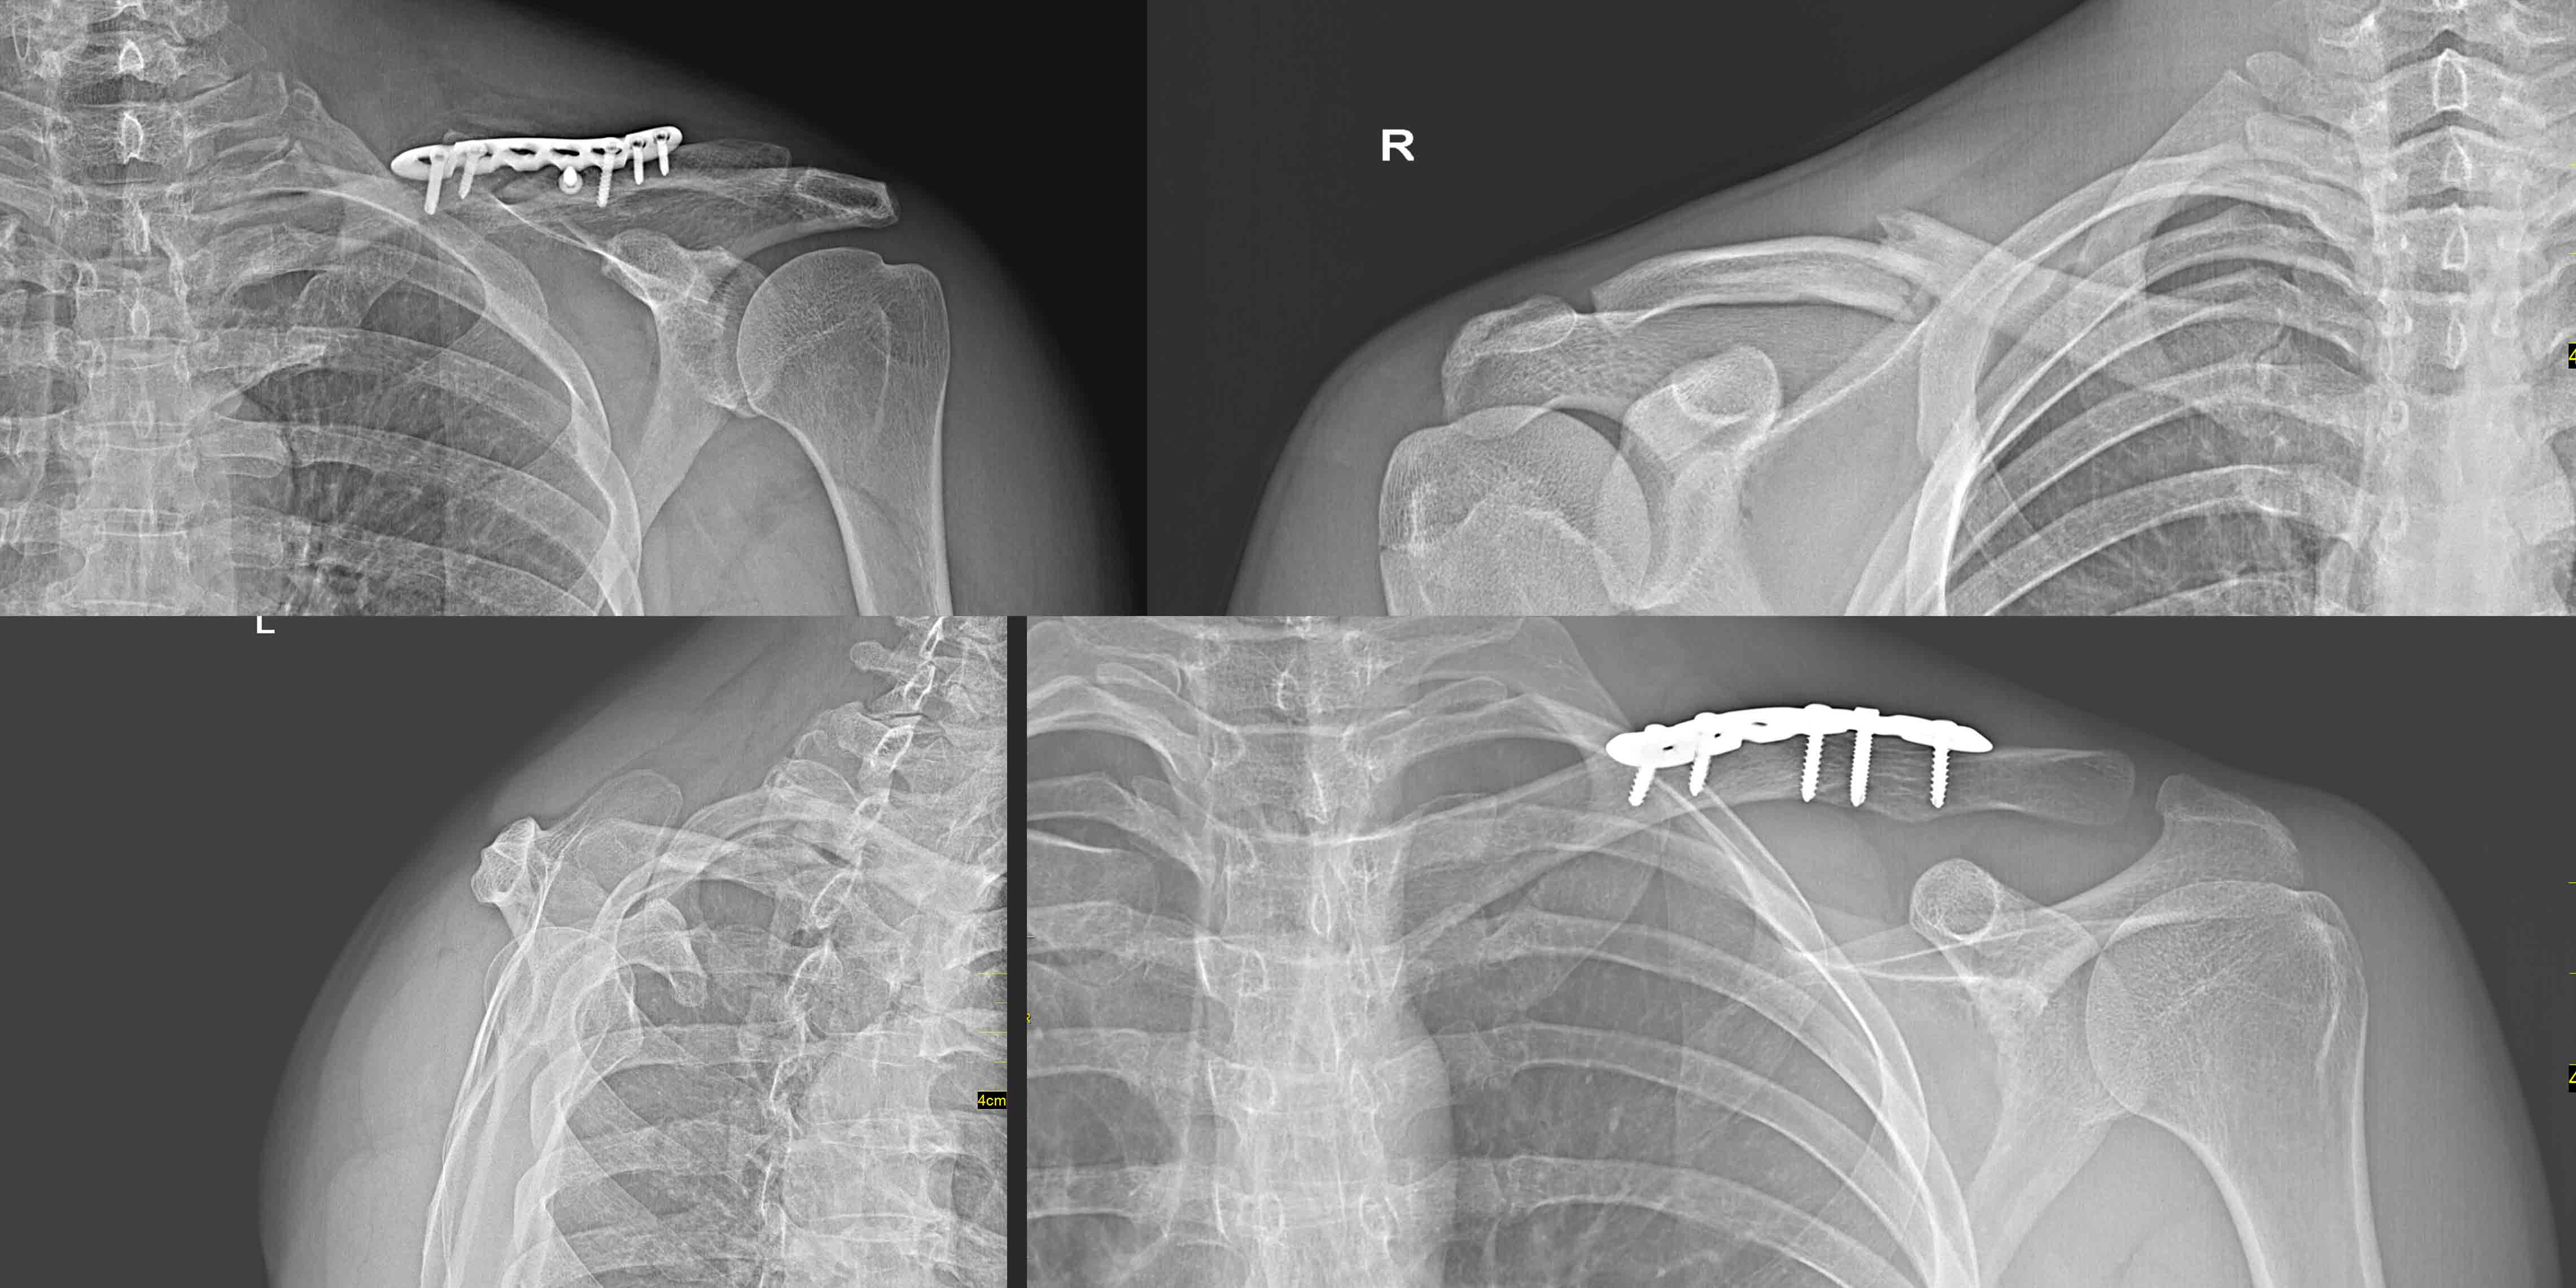

When there is significant displacement of the fragments during a clavicle fracture, the orthopedist usually recommends surgery. The procedure is performed under full anesthesia and involves open setting of the fragments with their stabilization with plates and screws. Since the metal plates are attached to the outer surface of the bone, and the clavicle lies directly under the skin, they can be felt. Normally, plates and screws are not removed once bone fusion is complete, as long as they do not cause discomfort. Occasionally, patients may experience irritation of the operated clavicle area when using a seat belt in a car or wearing a backpack. If this is the case, the metal components can be removed after the fracture has healed. It is important to remember that a natural part of the postoperative healing process is to feel pain. Therefore, it can be somewhat alleviated with ice packs and the use of painkillers and anti-inflammatory drugs prescribed by the doctor. A significant advantage of surgical treatment over conservative treatment is the shorter period of immobilization of the limb and the possibility of movement in the shoulder even as early as a week after surgery.